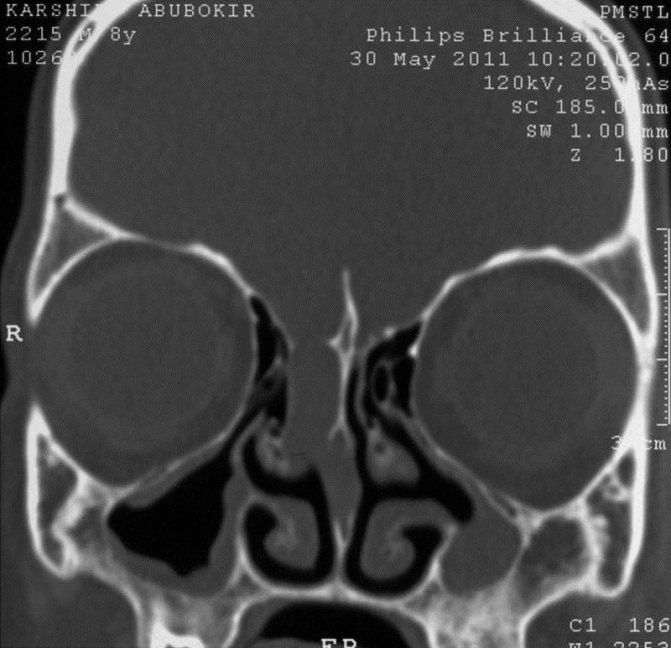

- Компьютерная томография (КТ) основания черепа и околоносовых пазух (на рисунке определяется большой дефект основания черепа в проекции ситовидной пластинки с формированием менингоцеле (показано стрелкой)).

- КТ черепа и головного мозга для исключения гидроцефалии, новообразований основания черепа, выявления менингоцеле.